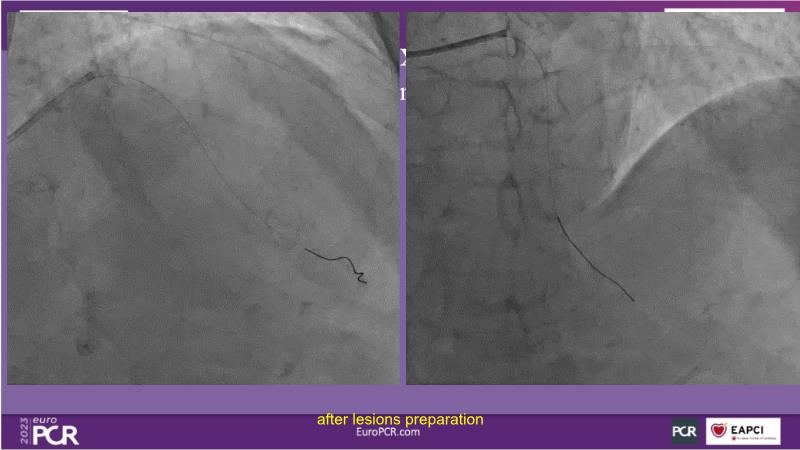

- To receive an in-depth insight into the latest clinical data and experiences on drug-coated balloon usage in in-stent restenosis, de-novo and bifurcation indications